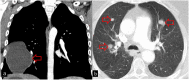

Hydatid cyst caused by the larval form of Echinococcus is a worldwide zoonosis. The lungs and liver are the most common sites involved. While the lung parenchyma is the most common site within the thorax, it may develop in any extrapulmonary region including the pleural cavity, fissures, mediastinum, heart, vascular structures, chest wall, and diaphragm. Imaging plays a pivotal role not only in the diagnosis of hydatid cyst, but also in the visualization of the extent of involvement and complications. The aim of this pictorial review was to comprehensively describe the imaging findings of thoracic hydatid cyst including pulmonary and very unusual extrapulmonary involvements. An outline is also given for the findings of complications and differential diagnosis of thoracic hydatid cyst.